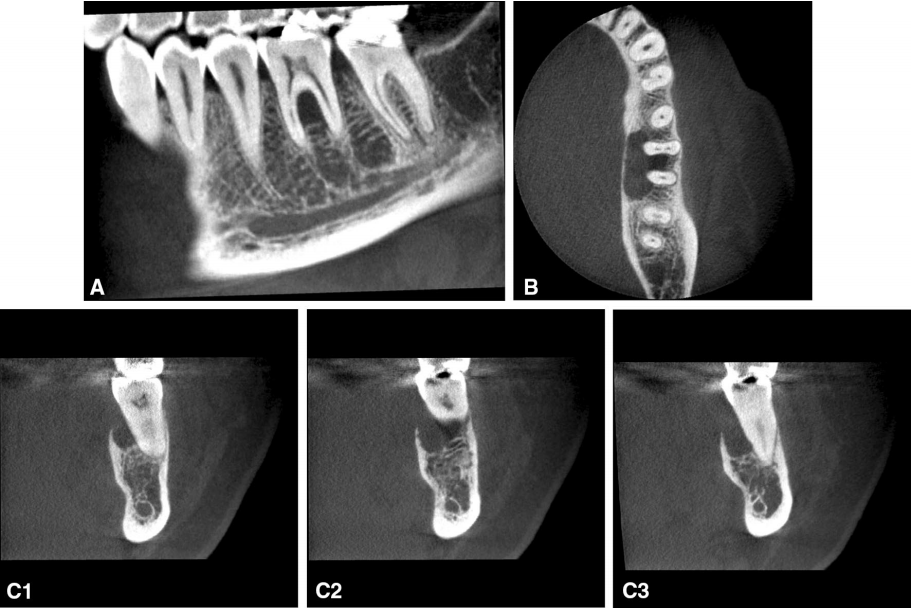

口外检查未显示肿胀、面部不对称或感觉异常。在头部和颈部,没有观察到淋巴结病变的临床证据。在口腔检查中,卵圆形肿块大小为12×20 mm,触诊质实,表面溃烂,并固定在下层组织上(图1A)。左下颌第一磨牙的活动度增加,但前磨牙和第二磨牙的运动度没有增加。用牙周探针进行的检查显示,除第一颗下磨牙外,上颌和下颌的牙槽正常(图1B)。用CO2干冰测试时,左后下颌的所有牙齿均呈阳性。患者口腔卫生良好。根尖周X线片显示第一磨牙周围的碗状透光区域。锥形束计算机断层扫描(CBCT)显示,第一磨牙舌侧沿牙根及其之间有一处透光性病变。单室溶骨性区域涉及骨的边缘和舌侧,并向牙冠侧开窗。边界定义不清(图2)。左侧第一磨牙或相邻牙齿没有牙根吸收的迹象。

图2. 左下颌骨的锥形束计算机断层扫描。可以观察到第一左磨牙的牙槽骨舌侧和牙根间的透光性。分界部分不清晰,开窗至顶部。